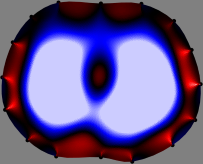

Figs. 3 and 4 compare the performance of the proposed FER method in (20) with the standard regularized least-squares method ((19) when is the identity matrix). The regularization parameter of the standard method was heuristically chosen for its best performance, and the parameter of the FER method was set to be one of three different values . The injection current was 1 mA at 100 kHz, and the frame rate was 9 frames per second. The reference frame at was obtained from the maximum expiration state. The measured data, , represent the voltage differences between each time and . The blue regions, which denote where conductivity decreased by inhaled air, increased during inspiration and decreased during expiration. The FER method with was clearly more robust than the standard method that produced more artifacts originated from the inversion process.

| Standard | |

||||||||||

| FER () | |